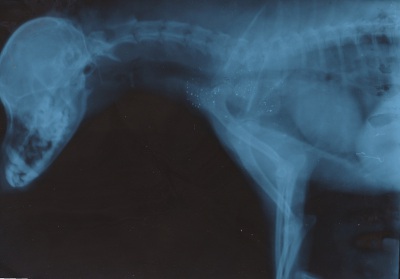

Коллапс трахеи форум